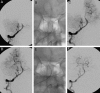

Background and purpose: Prompt recanalization of cerebral arteries in patients diagnosed with acute ischemic stroke is known to be associated with a better clinical outcome. The aim of this study was to present our initial experience regarding the efficacy and safety of the Solitaire FR as a revascularization device.

Methods: 56 consecutive patients presenting with acute ischemic stroke underwent intra-arterial therapy using the Solitaire FR revascularization device. Immediate angiographic results and early clinical outcomes are presented.

Results: Solitaire FR was successful in achieving recanalization in 50 out of 56 patients (89%) with a final Thrombolysis in Cerebral Infarction score ≥2b. Five out of 56 patients had procedure related complications: two asymptomatic subarachnoid hemorrhages, two thromboembolic events and one symptomatic intracranial hemorrhage (PH2). Thirty patients (53.5%) demonstrated at discharge a National Institutes of Health Stroke Scale Score of ≤1 or an improvement of at least 10 points from baseline, and 26 patients (46%) had a modified Rankin Score ≤2.

Conclusions: Solitaire FR is successful in achieving a high rate of arterial recanalization with a low complication rate. The Solitaire FR is a promising thrombectomy tool with a high degree of effectiveness, safety and ease of use.